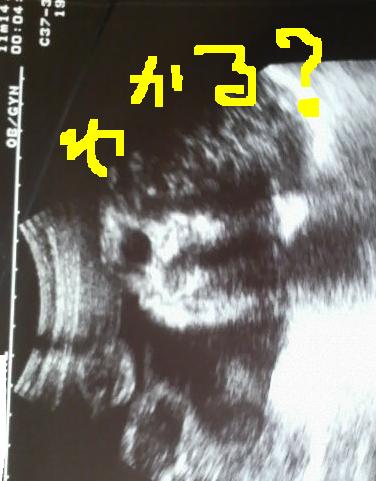

ちょうど顔がはっきり映ってる所を撮ってくれたんだよ~

コレダ!!

ジローのお顔♪  お顔解説w

どう?(*´∀`)

鼻がねぇ~アオサンそっくりなの!!